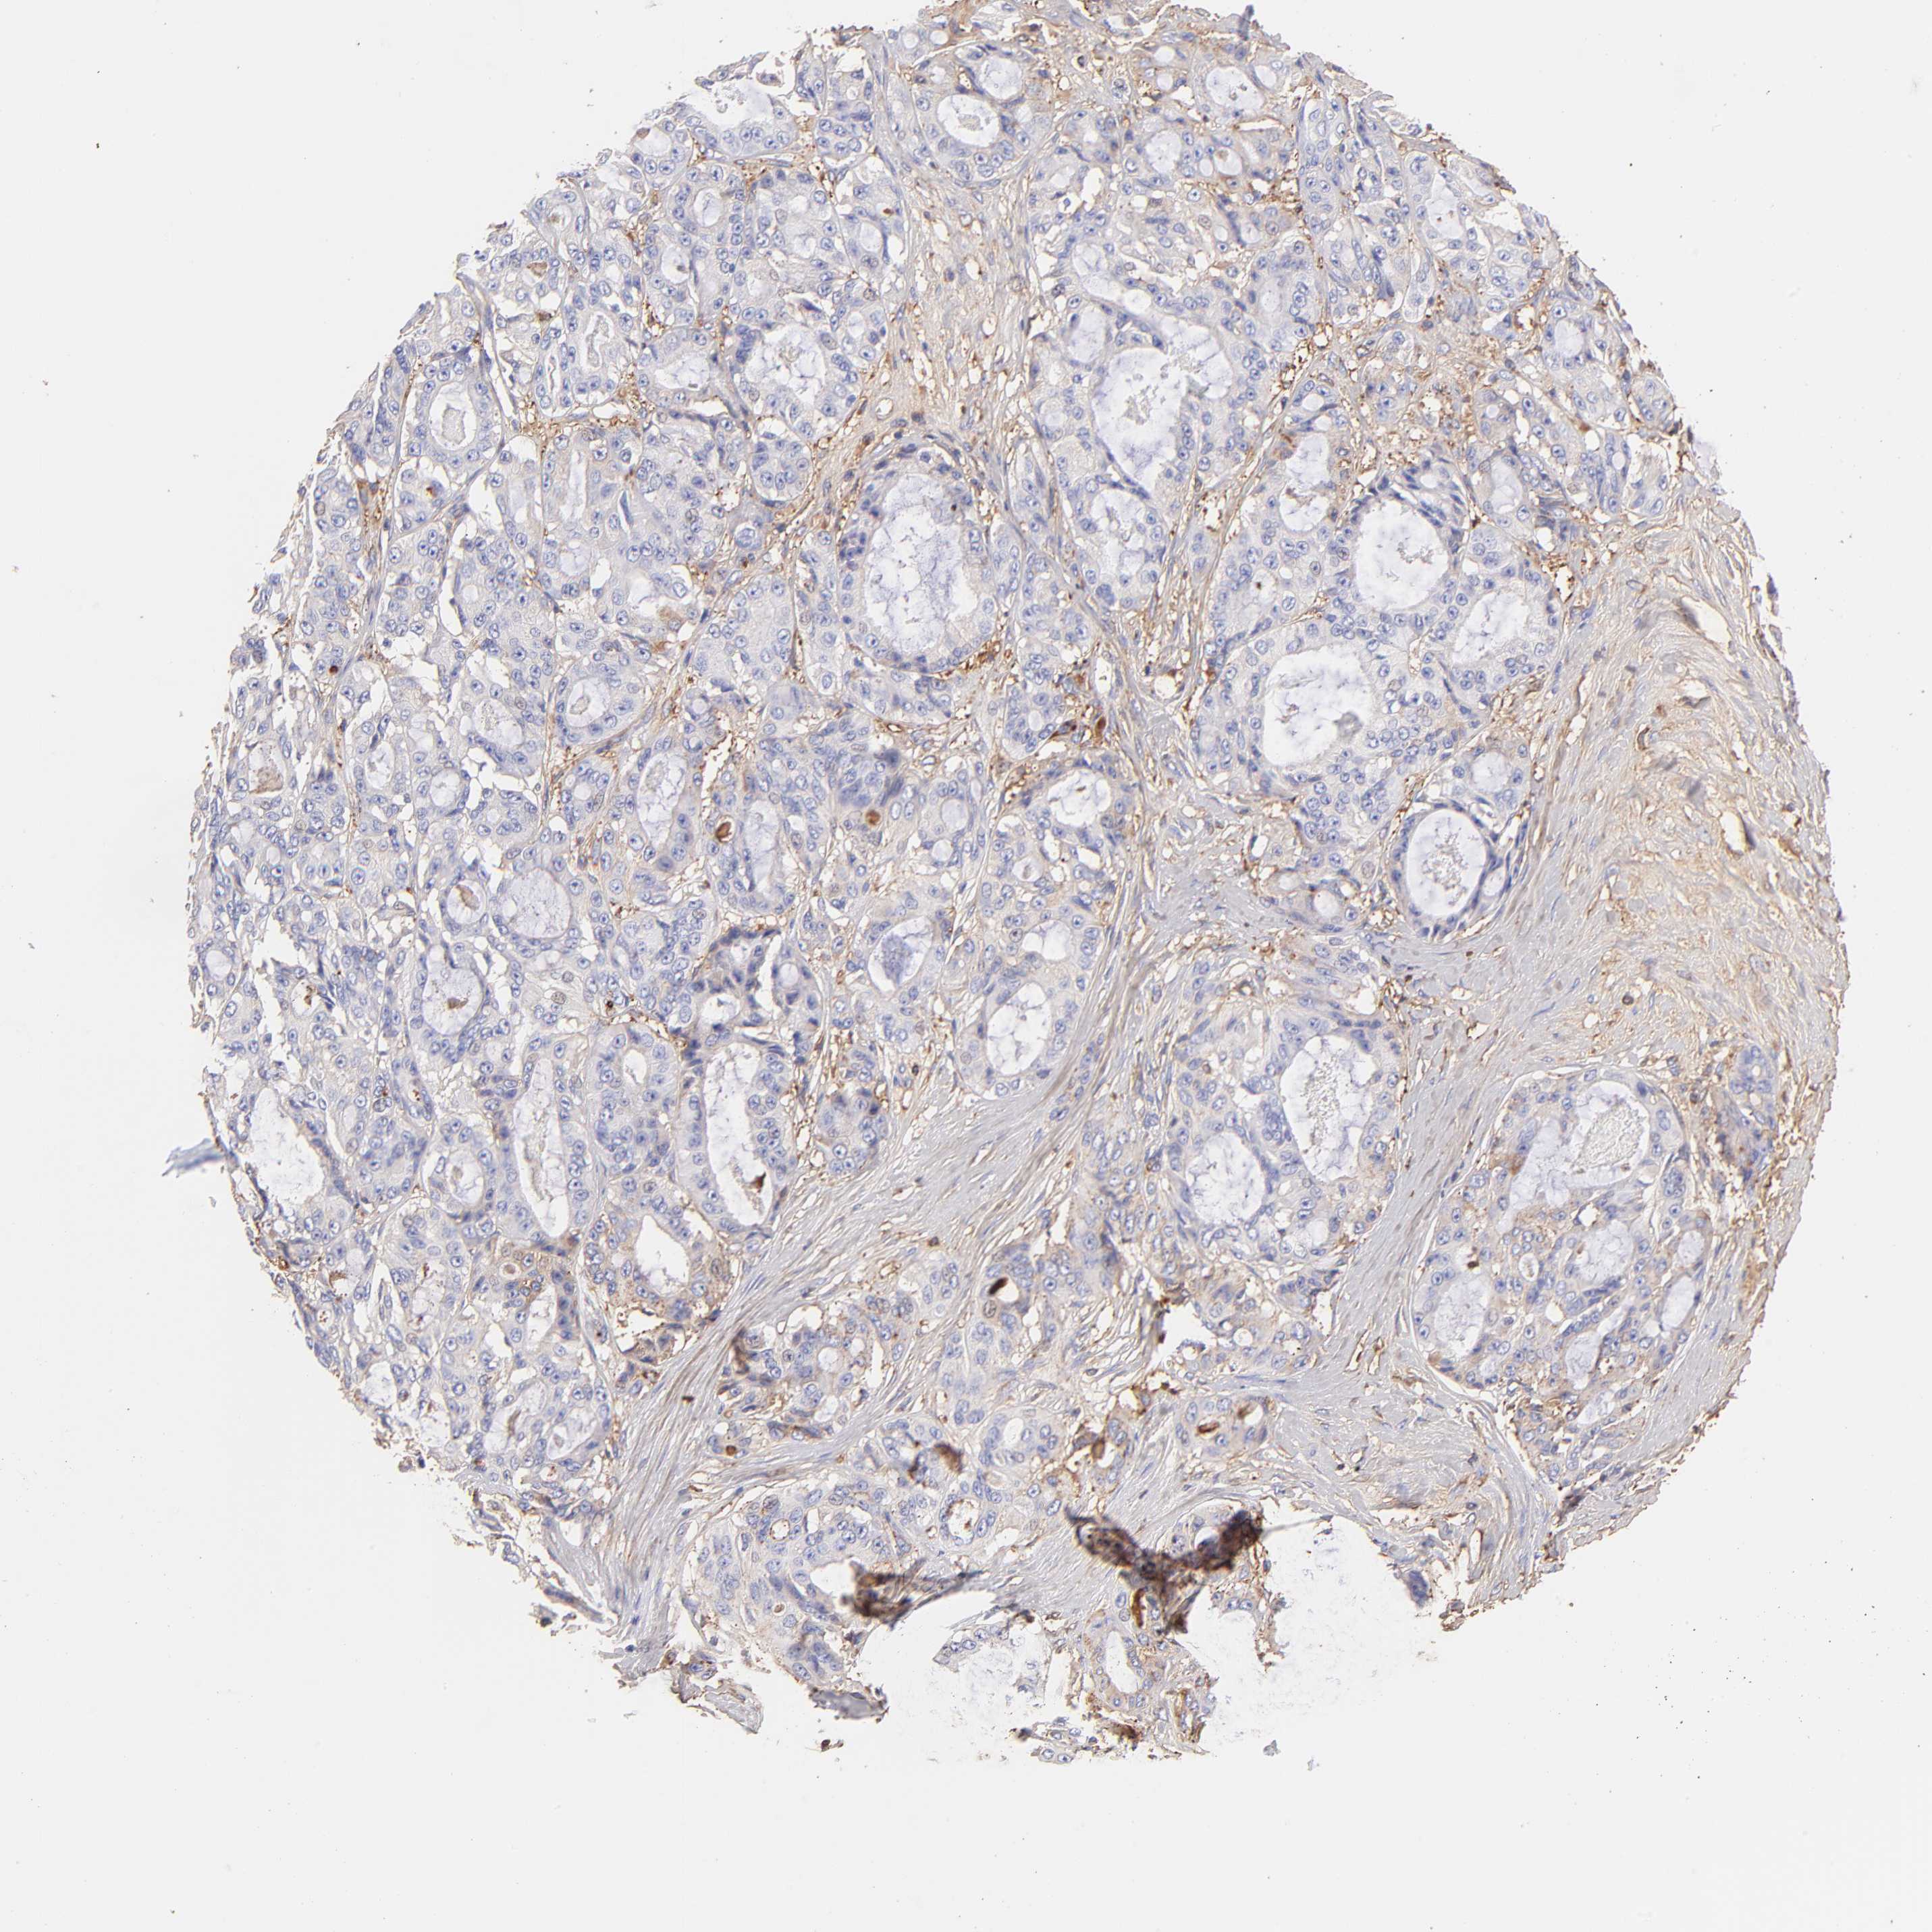

OVARIAN CANCER - Protein expressioni

A mouse-over function shows sample information and annotation data. Click on an image to view it in a full screen mode. Samples can be filtered based on level of antibody staining by selecting one or several of the following categories: high, medium, low and not detected. The assay and annotation is described here.

Note that samples used for immunohistochemistry by the Human Protein Atlas do not correspond to samples in the TCGA dataset.

Antibody stainingi

Antibody staining in the annotated cell types in the current human tissue is reported as not detected, low, medium, or high, based on conventional immunohistochemistry profiling in selected tissues. This score is based on the combination of the staining intensity and fraction of stained cells.

Each image is clickable and will lead to virtual microscopy that enables deeper exploration of all samples and also displays staining intensity scores, fraction scores and subcellular localization as well as patient and tissue information for each sample.

Antibody HPA003157

Antibody CAB003678

Staining

High

Medium

Low

Not detected

Intensity

Strong

Moderate

Weak

Negative

Quantity

>75%

75%-25%

<25%

None

Location

Nuclear

Cytoplasmic/membranous

Cytoplasmic/membranous,nuclear

Carcinoma, endometroid

Cystadenocarcinoma, serous, NOS

Cystadenocarcinoma, mucinous, NOS